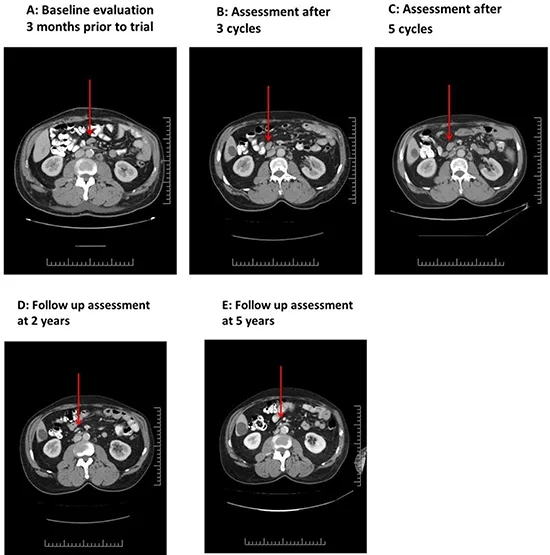

NK-92治疗前的CT扫描显示:双侧腋窝最大淋巴结长径达2.5cm,同时存在1cm大小的肠系膜淋巴结及腹主动脉旁淋巴结(图1A)。第1疗程NK-92治疗第23天中期评估显示病情稳定,最大腋窝淋巴结略缩小;3个疗程后影像学提示部分淋巴结缩小、部分增大(图1B);5个疗程后淋巴结持续增大,且脾脏从基线12.7cm(图2A)增大至15.3cm(图2B),因影像学提示疾病进展,患者停止治疗。停药后患者未接受其他抗癌治疗,CT扫描随访发现,24个月后所有病灶均消退(图1D、1E,图2C)。后续患者曾因降压药出现血小板减少症(经泼尼松+环孢素治疗好转),约1年后因皮肤带状疱疹感染继发急性播散性脱髓鞘性脑脊髓炎(经激素治疗后,6个月缓慢减量,神经功能完全恢复)。此后患者未再接受抗癌治疗,入组试验10年后的最近一次随访显示,其临床与影像学检查均无疾病迹象,且无任何不适症状。

▼图1 患者03在NK-92细胞治疗前后肠系膜淋巴结的CT对比

▲图源“Oncotarget”,版权归原作者所有,如无意中侵犯了知识产权,请联系我们删除